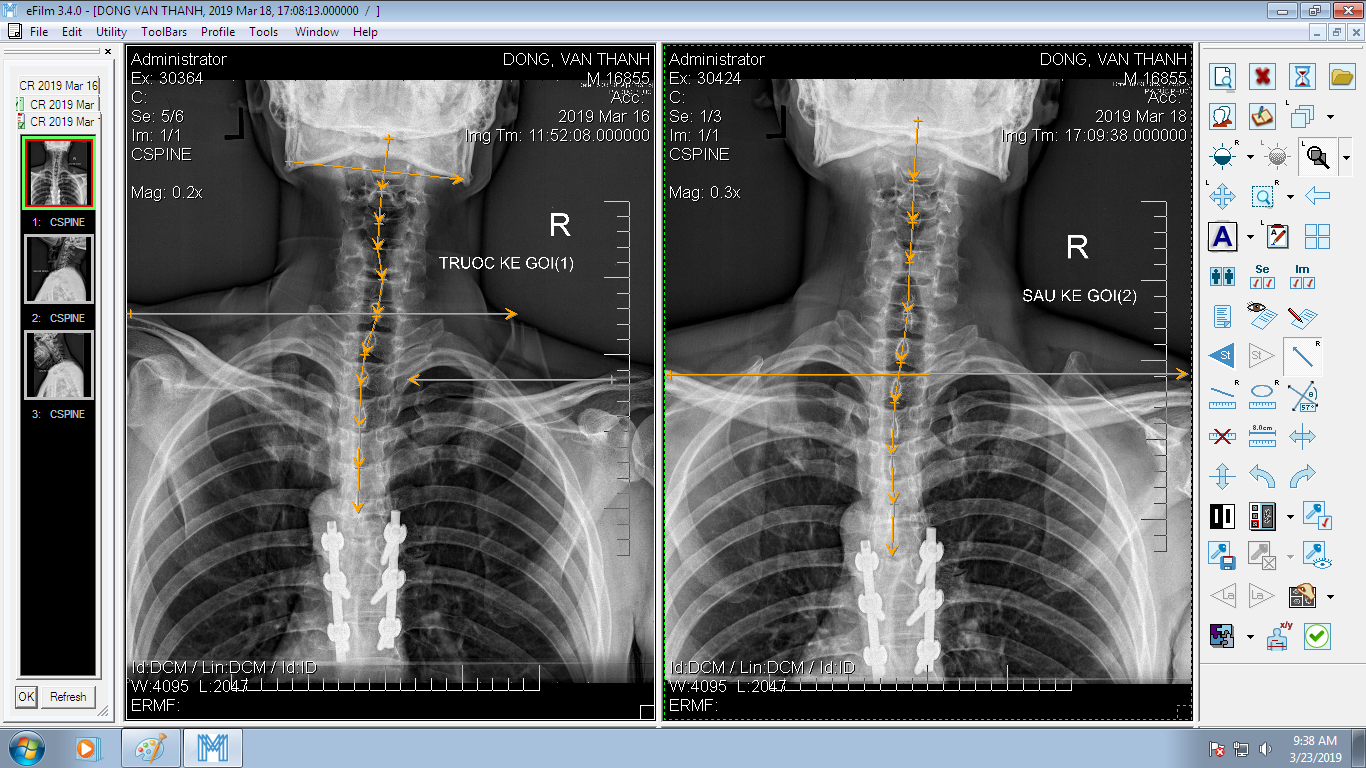

DOCTORLOAN đã thành công trong điều chỉnh xương khớp về đúng vị trí trong thời gian ngắn